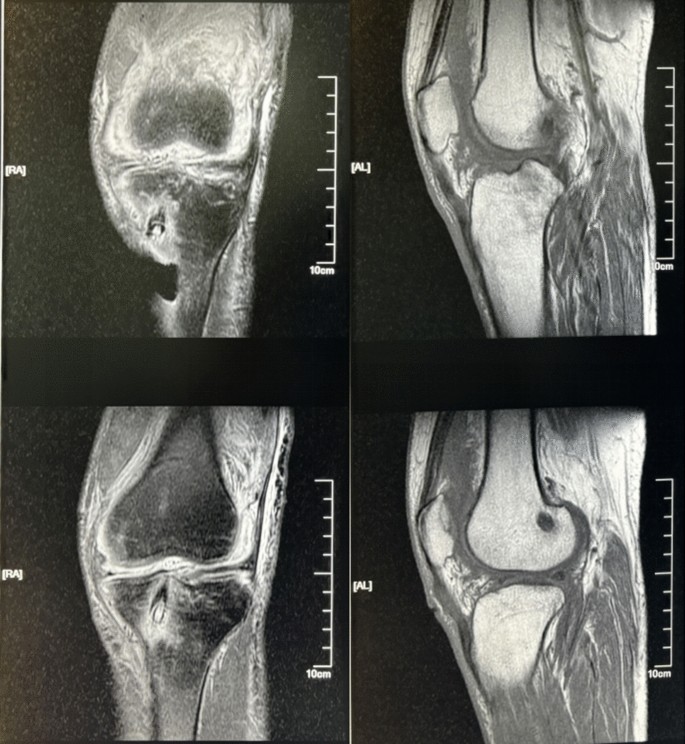

Of the 1500 patients, 20 were infected after ACLR surgery. We screened 1500 patients who were diagnosed with postoperative infection of the ACL according to the inclusion criteria. The diagnostic conditions of the infection were as follows: (1) Pain and swelling: patients who experienced significant pain and swelling in the limb after surgery. (2) Limited Mobility: the knee joint exhibited limited flexion and extension. (3) Skin changes: localized increase in skin surface temperature with associated redness. (4) Systemic inflammatory signs: body temperature ≥ 38 °C, chills and general fatigue. (5) Joint puncture: the presence of purulent fluid aspirated via joint puncture. (6) Inflammatory markers: CRP ≥ 20 g/L, white blood cell (WBC) count ≥ 10 × 109/L, and neutrophil percentage ≥ 90%. (7) Microbial evidence: positive bacteria detection after puncture of the knee joint or tendon removal site. The 7th diagnostic criterion is the gold standard for the diagnosis of suppurative arthritis. If there are two or more items in numbers 1–5, laboratory examination and observation of inflammatory indicators are necessary. After screening, 20 patients met the criteria. Table 1 shows the data of infected patients after anterior cruciate ligament reconstruction before the second operation. Patients 1–4 and 10–20 were infected within the joint, and patients 5–9 were infected at the incision of the tendon (Figs. 1, 2).